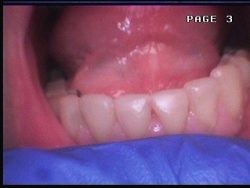

LECZENIE I ODBUDOWA ZNISZCZONYCH PRÓCHNICĄ TKANEK ZĘBA

Niestety, czasem pomimo mycia zębów oraz dbania o higienę jamy ustnej bakterie wygrywają z zębami. Powstaje ubytek tkanek zęba. Aby zapobiec dalszemu zniszczeniu struktury szkliwa i zębiny konieczne jest usunięcie próchnicy. Gdy usuniemy próchniczo zmienione tkanki zęba, miejsce w którym była próchnica wypełniamy specjalistycznym materiałem. Potocznie Pacjenci nazywają to „założeniem plomby”.

Wypełnienie kompozytowe jest tym, co pacjenci zwykli potocznie nazywać białą plombą.

Po oczyszczeniu zęba z próchnicy, lekarz uzupełnia brakujące tkanki zęba wypełnieniem pozwalającym przywrócić w sposób maksymalnie zbliżony do naturalnego stanu pierwotny kształt i kolorystykę zęba.